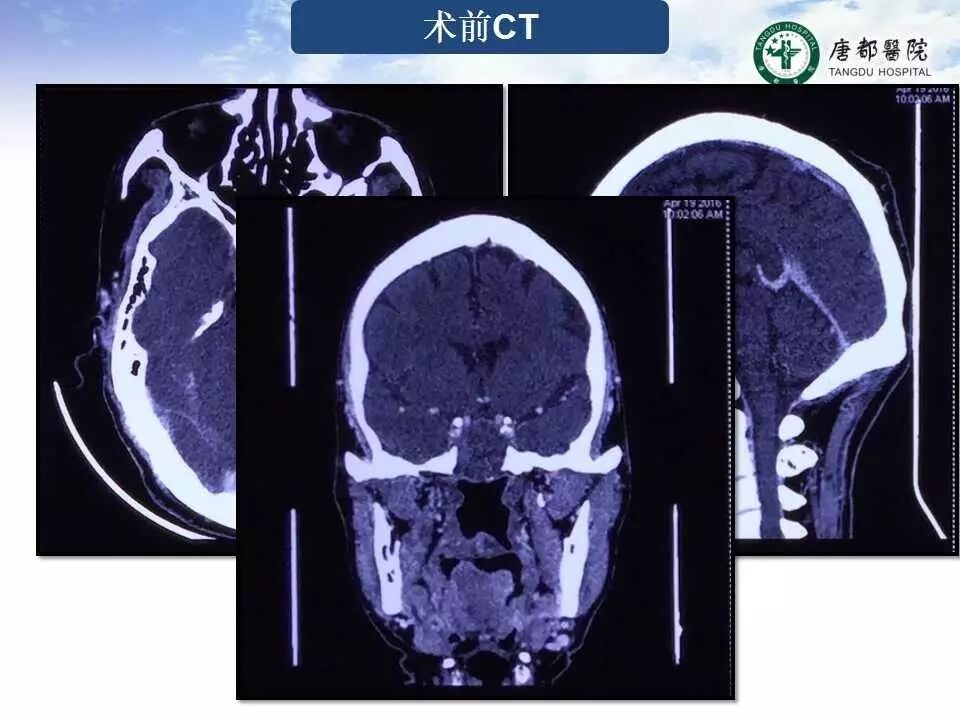

Case 3

长按并识别二维码即可查看该手术视频